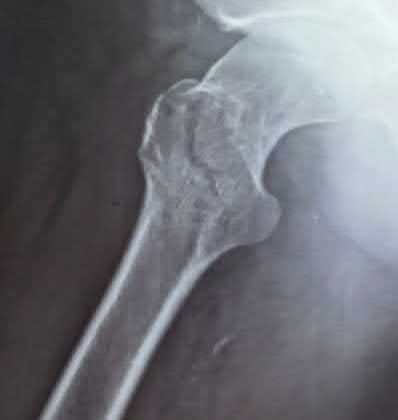

Question 9:

A 30-year-old male sustains a severe midfoot sprain. Radiographs reveal widening between the bases of the first and second metatarsals. The primary ligamentous stabilizer disrupted in this classic Lisfranc injury connects which two osseous structures?

Correct Answer: Medial cuneiform to 2nd metatarsal base

Explanation:

The Lisfranc ligament is the strongest ligament in the tarsometatarsal joint complex. It courses obliquely from the lateral aspect of the medial cuneiform to the medial base of the second metatarsal. It acts as the primary stabilizer of the second metatarsal base. Disruption results in the classic widening between the first and second rays, often with an avulsion fragment ('fleck sign').